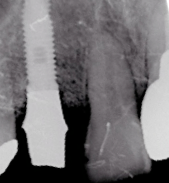

光機能化インプラントの実際の写真

光機能化を行うとインプラントの濡れがよくなり血液が付きやすくなります

血液に触れた瞬間からネジやまに血液が上がってきているのがわかるとおもいます

これによりインプラントの骨に結合する強さ、早さが劇的に改善し、

より患者さんに自信をもってインプラント治療を提供すること可能となりました。